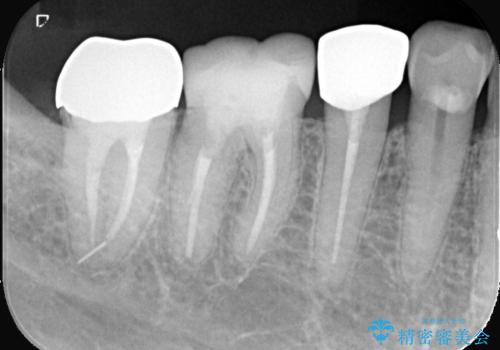

失活歯に保険適応のメタルクラウンがセットされていました。

根尖病巣と根管内に破折ファイルを認め、ファイル除去は困難だということをお伝えし、根管治療・土台・クラウンのやり替えとなりました。

根管内破折ファイルの除去が難しいことから、近心根根尖部の洗浄が十分には行えない(病巣が消えない可能性がある)ことを了承いただき治療となりました。